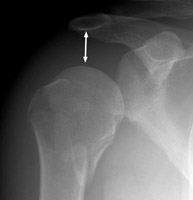

Two views of the right shoulder in this post-traumatic patient with a fracture of the proximal humerus. Note the downward displacement of the humerus and it's relation to the acromio-clavicular joint and the glenoid. The drooping shoulder occurs following fracture of the surgical neck and may be secondary to hemarthrosis or musculoligamentous injury. Other non-traumatic causes such as stroke and brachial plexus compromise from a tumor have been described as well.

AP shoulder - Click on the image for a larger versionAAxillary view - Click on the image for a larger versionB